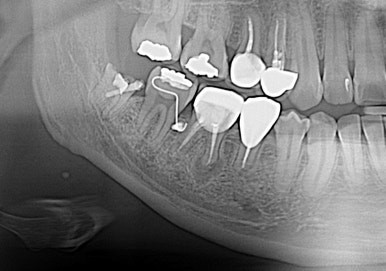

사랑니 뿌리가 신경관과 근접

교정력을 주어 열심히 당기기 한 달 별다른 위치변화가 보이지 않아서 좀 답답하다...